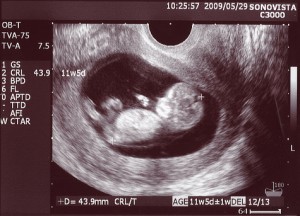

Une échographie à 11 semaines montrera les contours clairement visibles du petit homme. Sur un équipement haut de gamme avec une localisation particulièrement bonne du bébé, vous pouvez déjà déterminer son sexe. Cependant, les données peuvent être inexactes.

Photo échographie: